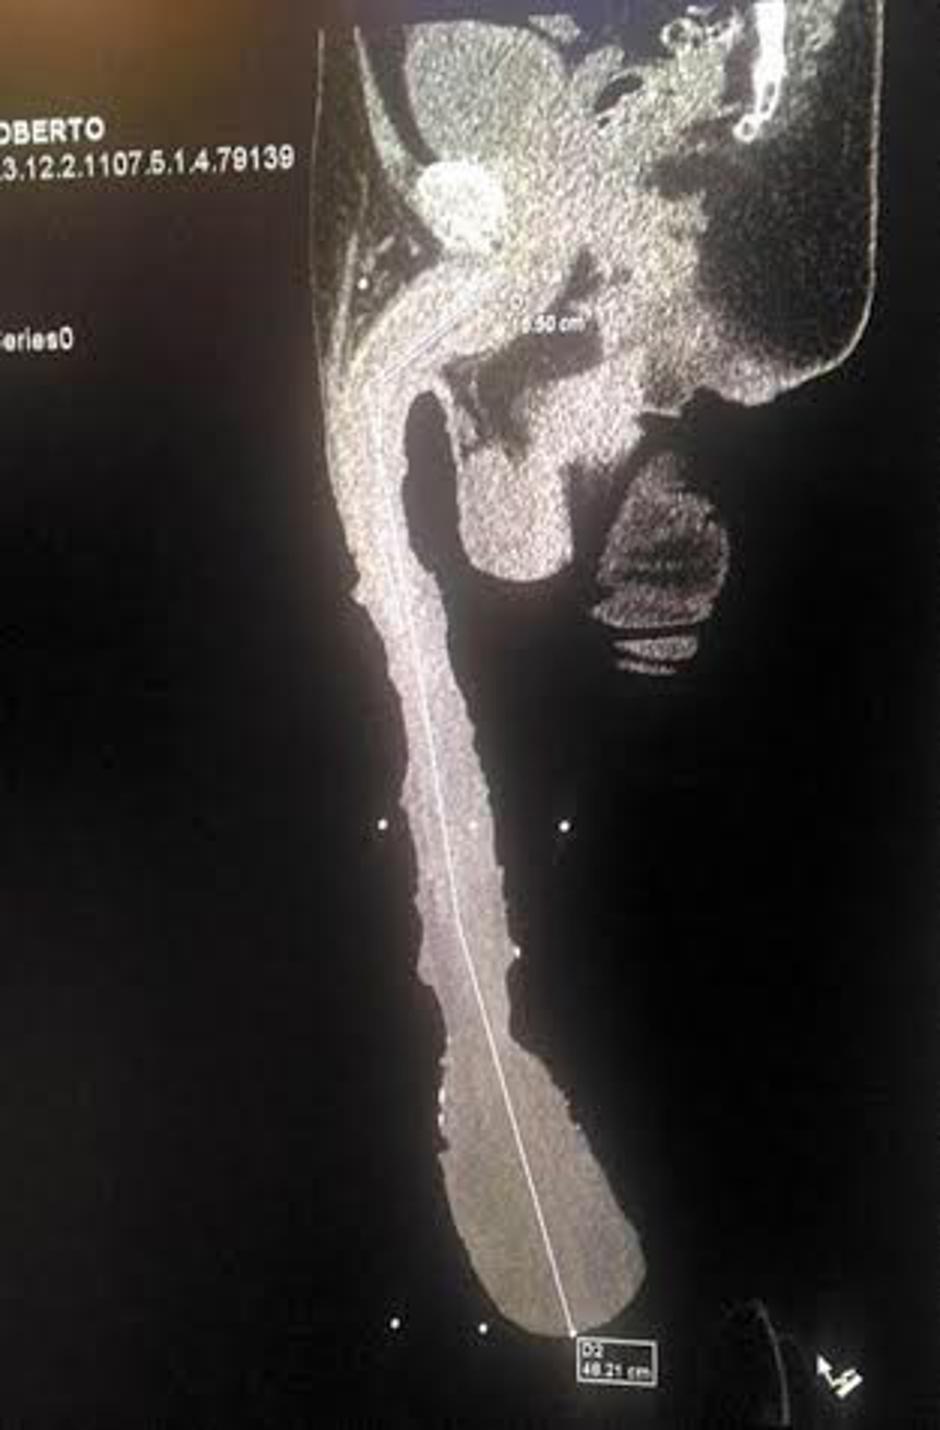

"Želim se vpisati v Guinnessovo knjigo rekordov, v kategorijo človek z najdaljšim penisom na svetu," je nedavno medijem zaupal Roberto Esquivel Cabrera, Mehičan, ki pravi, da je njegovo splovilo dolgo 48,3 centimetra največje na svetu, v dokaz za to pa priloži rentgensko sliko.

Kot piše angleški The Sun je Robertu skoraj pol metra dolg organ uničil življenje: "Poglejte vendar, kakšen je! Visi mi izpod kolen! Nič ne morem početi. Ker sem nesposoben, bom od države zahteval pomoč in status invalida," je dejal nesrečnik in dodal, da si želi, da bi ga v Guinnessovi knjigi priznali kot rekorderja. Cabrera je ob tem potarnal, da si nikakor ne more najti partnerice, saj si nobena z njim ne želi imeti spolnih odnosov,